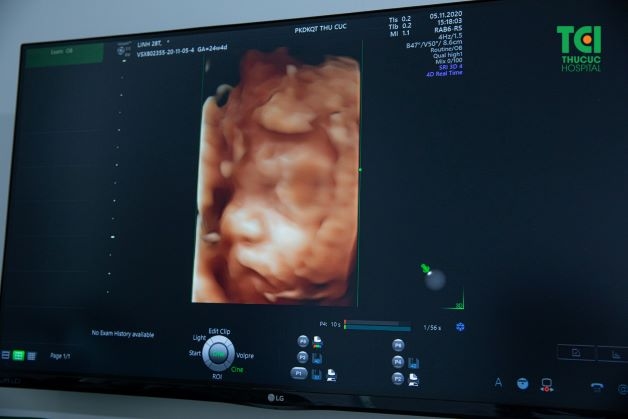

– Siêu âm thai 3D: Hình ảnh hai chiều được chụp ở nhiều góc độ khác nhau sau đó được tập hợp lại để tạo thành hình ảnh 3 chiều hay còn gọi là siêu âm 3D.

– Siêu âm thai 4D: tương tự như siêu âm 3D, nhưng ưu việt hơn so với phương pháp cũ vì mẹ có thể quan sát rõ nét hơn mọi cử động và biểu cảm của thai nhi trong bụng (mút tay, lè lưỡi…).

– Siêu âm thai 5D: là hình thức siêu âm kết hợp của siêu âm 4D và phương pháp siêu âm màu Doppler. Đây là công nghệ hiện đại giúp quan sát một cách rõ nét và chân thực hình thái, cử động của thai nhi trong bụng mẹ. Đồng thời giúp bác sĩ chẩn đoán, phát hiện sớm các dị tật ngay từ những tháng đầu tiên của thai kỳ.

Hệ thống máy siêu âm 5D phiên bản mới tích hợp những tính năng hiện đại, nhờ đó các mẹ có thể dễ dàng quan sát rõ nét thế giới của con yêu trong suốt thai kỳ

Bên cạnh những công nghệ siêu âm 3D, 4D, công nghệ siêu âm 5D hiện đại đã được Thu Cúc TCI cập nhật và đưa vào sử dụng, chắc chắn sẽ mang đến cho các mẹ bầu những trải nghiệm tuyệt vời trong suốt thai kỳ. Hệ thống máy siêu âm 5D phiên bản mới tích hợp những tính năng hiện đại, nhờ đó các mẹ có thể dễ dàng quan sát rõ nét thế giới của con yêu trong suốt thai kỳ.

– Màn LED 23 inch mang đến những hình ảnh rõ ràng, sắc nét từng hành động, cử chỉ thai nhi.